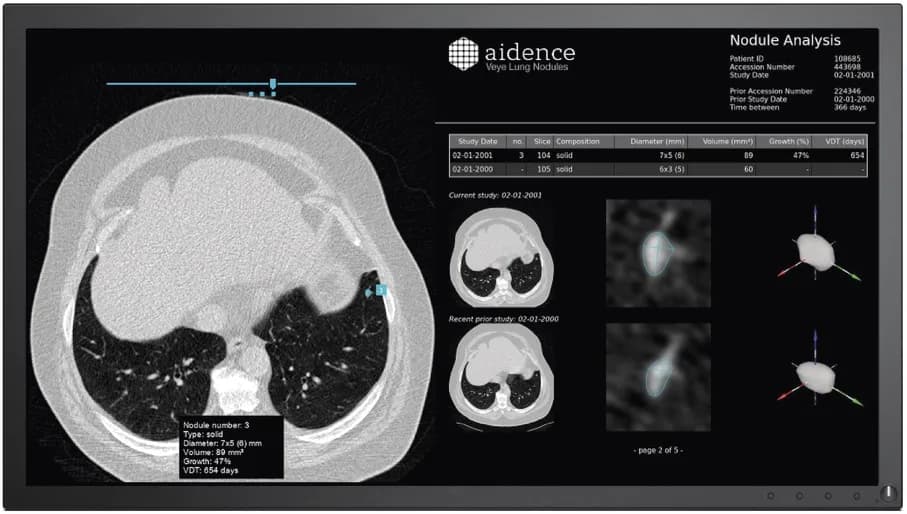

Amsterdam-based Aidence combines data science and healthcare by developing artificial intelligence solutions for the field of oncology. Their first tool, Veye Lung Nodules, helps radiologists identify and characterise pulmonary nodules – small growths on the lung – and track their progression. These nodules, particularly if they change size or shape over time, could be cancerous and catching these markers early can help increase survival rates. A recent NELSON study showed that CT screening for nodule volume management reduces lung cancer mortality by 26%, and more research is underway to further explore the impact of CT screening in improving patient outcomes.

By automating this process, Veye Lung Nodules can save radiologists time and energy that they could instead channel into assessing the findings and caring for their patients. Lung cancer is one of the most common and deadly cancers so faster detection could save hundreds of thousands of lives each year. The Aidence team trained the Veye Lung Nodules algorithms by feeding thousands of CT chest scans from a variety of data sets and then checking that data against approximately 1000 cases annotated by 3 expert radiologists.

Eventually the algorithm was able to independently learn and improve on its ability to identify the characteristics of nodules, noting their size, volume and opacity. It also automatically checks a patient’s previous scans to determine if the growths have changed size or shape over time. This simplifies reporting and helps radiologists supply all the most relevant data to referring physicians.